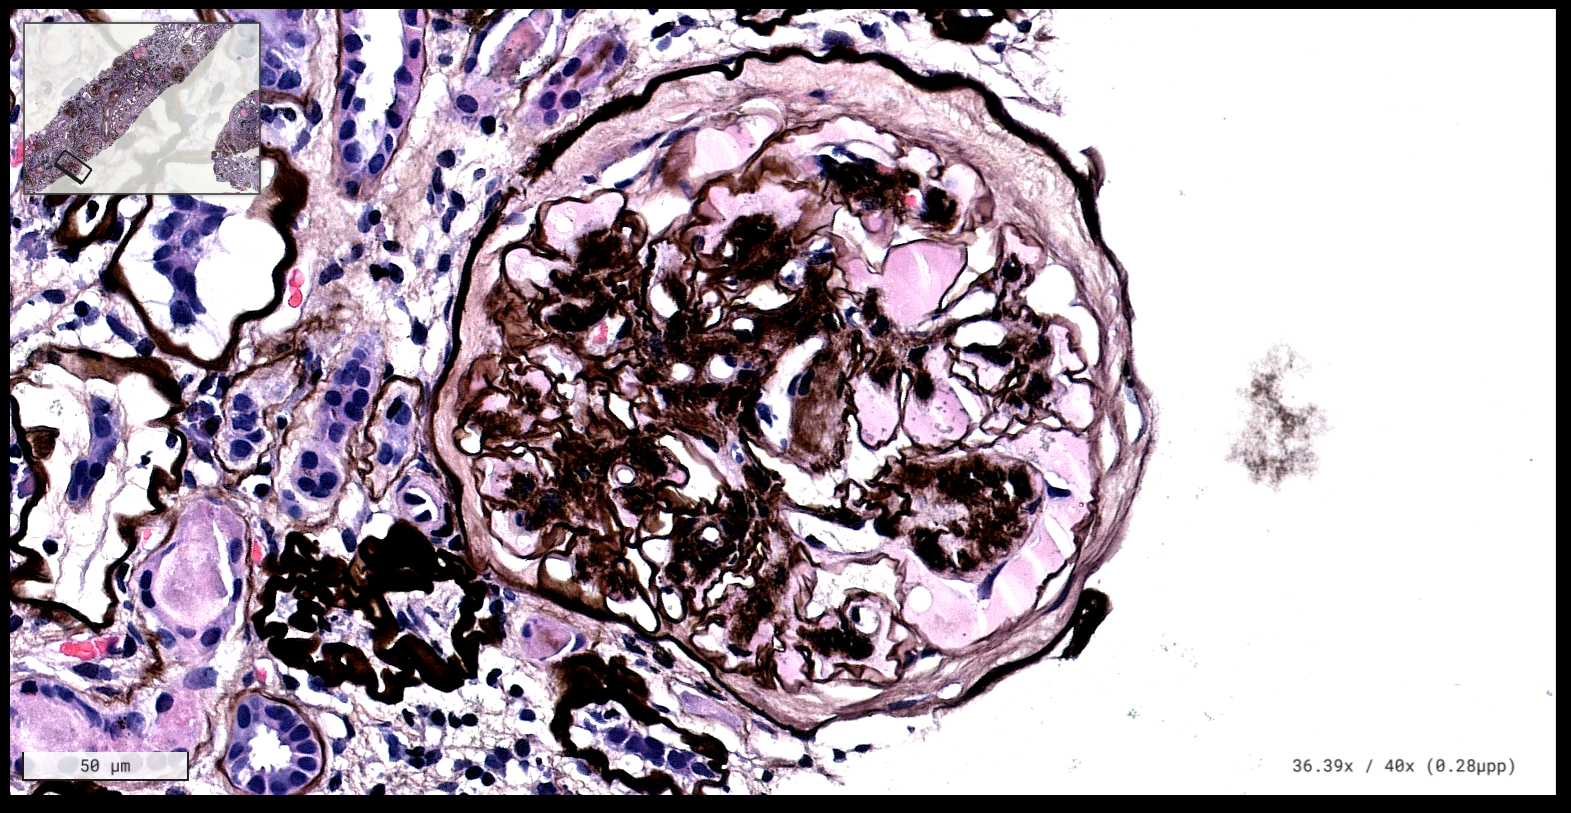

Patología Molecular

El diagnóstico sobre muestras de tejidos y líquidos corporales en plena era de la medicina del futuro, está basado en la integración de técnicas y conocimientos diferentes.

Hoy más que nunca es importante integrar una buena historia clínica con un correcto estudio de imagen y una buena morfología que además puede estar apoyada con proceso especiales complementarios relacionados con la Inmunología, Biología Molecular y Citogenética, generando así un estudio integral conocido como Patología Molecular.